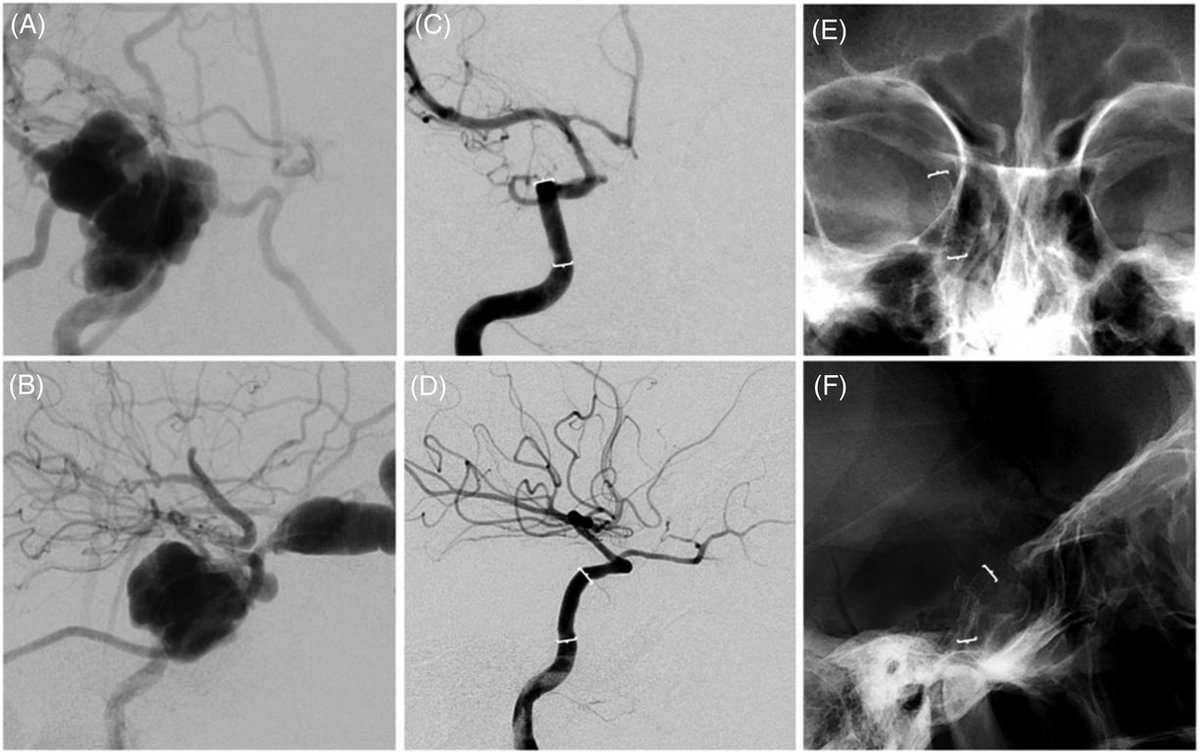

#AI LVO detection = 11.2 min faster EVT in our randomized trial. Very thankful to my co-author Youngran Kim, mentor @SunilAShethMD and all @UTHoustonStroke team. Consider sharing @JAMANeuro